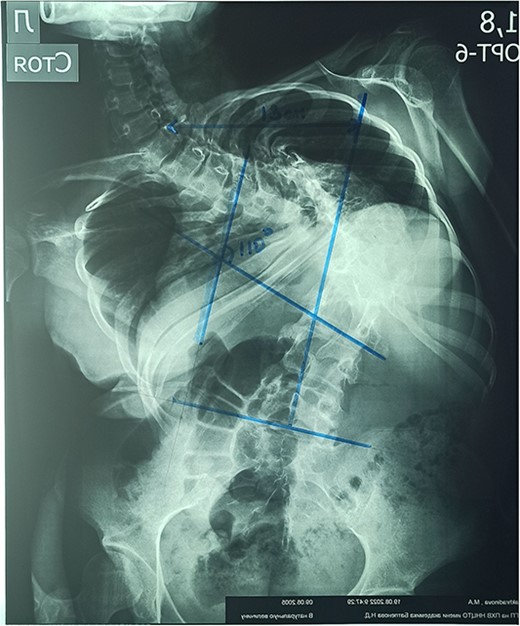

On the preoperative anterior–posterior X-ray, the Cobb angle was 110°; violation of frontal balance—13 cm (Fig. 2).

The rigidity of the scoliotic arch is noted on functional X-rays and on stretching (Fig. 3).